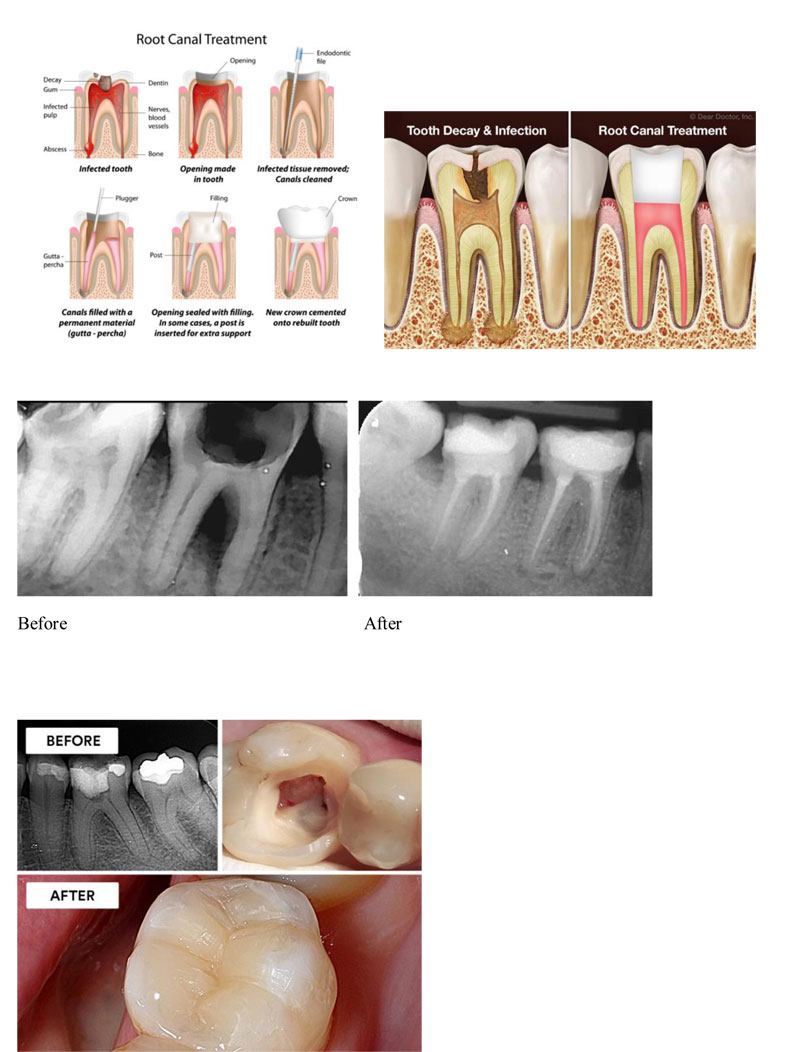

Root canal treatment, also known as endodontic therapy, is a common dental procedure used to save teeth that are severely infected or damaged. It is performed when the pulp, the soft tissue inside the tooth, becomes infected or damaged. This can occur due to deep cavities, cracks, or trauma. Without treatment, the infection can spread, leading to severe pain, abscesses, or even tooth loss.

We understand that dental procedures can be anxiety-inducing, which is why we aim to make the experience as comfortable as possible.Our experienced dentists will evaluate your tooth and take necessary X-rays to determine the extent of the damage. We will numb the area around your tooth to ensure a pain-free procedure. In all cases, a crown is placed on the tooth after the root canal treatment to restore its strength and function. Root canal treatment is often effective in preserving a tooth, preventing the need for extraction, and alleviating pain caused by infection.